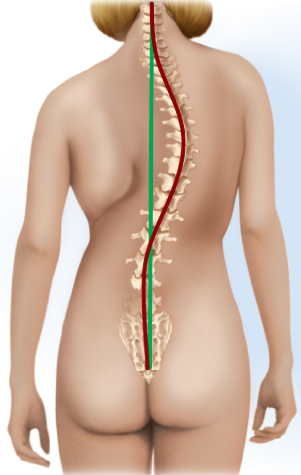

Scoliosis

Lateral (S shape, side-to-side), thoracic region